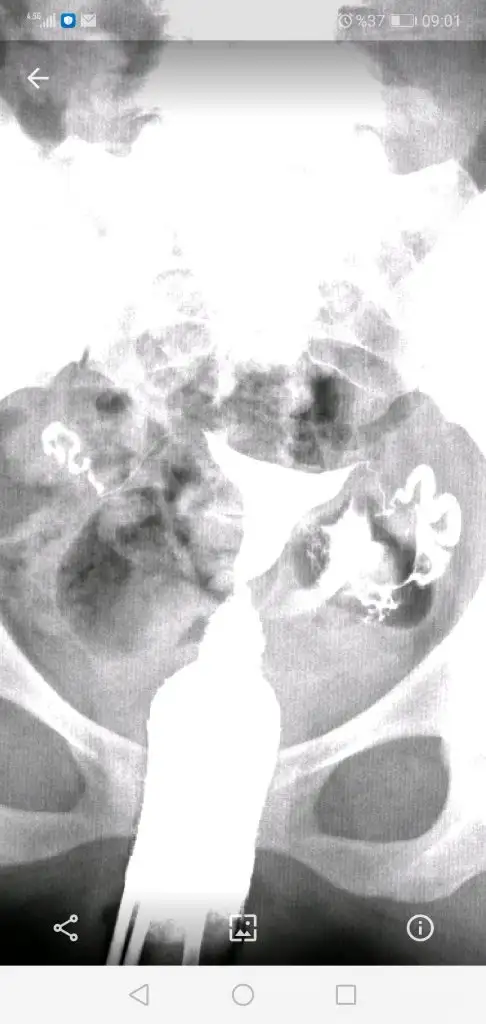

Doktorla konuştuk şimdi. Sol tamamen açık sıkıntı yok, sağda da yapışıklık varmış yüzde 90 ihtimalle açılmış. Sıkıntı görünmüyor geçiş var yani. Şuan hsg çeksek o da sıkıntısız çıkar yüksek ihtimal dedi. Emin olmak için laparoskopi yapabiliriz isterseniz ama bence 6 ay deneyin ben açıldığını düşünüyorum dedi. Bi de 1 ay korunun dedi ama ben korunmucam. Bu arada e nabızdan indirdiğim görüntü bu burda daha net görülüyor geçiş olduğu U Uzaygemisi35